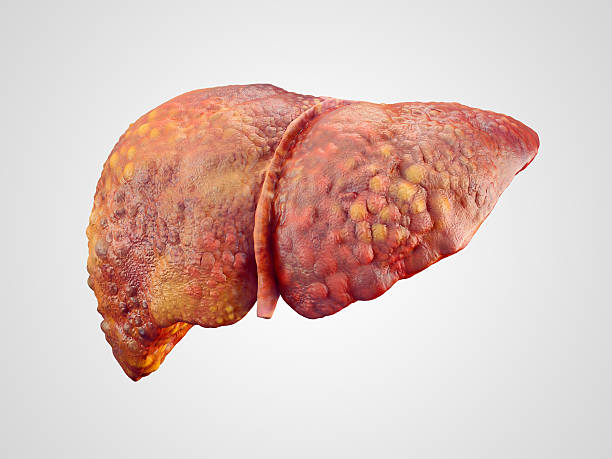

간경화 초기증상 10가지 총정리

간경화 초기증상은 증상이 나타나지 않거나, 미미한 증상만 나타나기 때문에, 무시하고 지나치기 쉬운 경우가 많습니다. 하지만, 이러한 초기 증상을 간과하면 질병이 진행되어 치료가 어려워질 수 있습니다. 따라서, 간경화 초기증상을 발견하면 적절한 검사와 치료를 받아 조기에 질병을 예방하고 치료할 수 있습니다. 따라서 이번 시간에는 간경화 초기증상에 대해 자세히 알아보도록 하겠습니다.